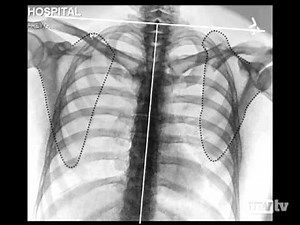

Clavicle and Scapula Fractures - S…

YouTubeAtlantic Health